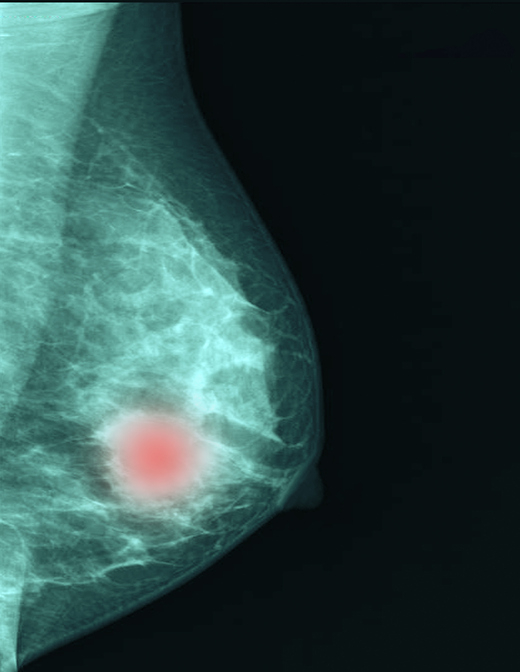

국내 여성암 발생 1위를 달리는 유방암은 환자가 지닌 '인자' 유무에 따라 여러 아형(subtype)으로 분류된다. 유전자를 이용한 첨단 검사법이 활용되면서, 분류에 따른 치료 방향이 더욱 정밀해지고 있다.